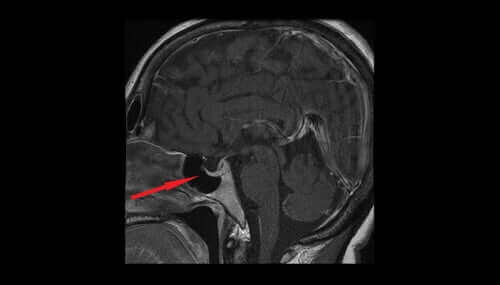

Alhainen antidiureettisen hormonin pitoisuus saa munuaiset erittämään liikaa vettä. Virtsan määrä lisääntyy ja johtaa kuivumiseen ja verenpaineen laskuun. Antidiureettisen hormonin alhainen pitoisuus voi olla merkki hypotalamuksen tai aivolisäkkeen vauriosta tai primaarisesta polydipsiasta.